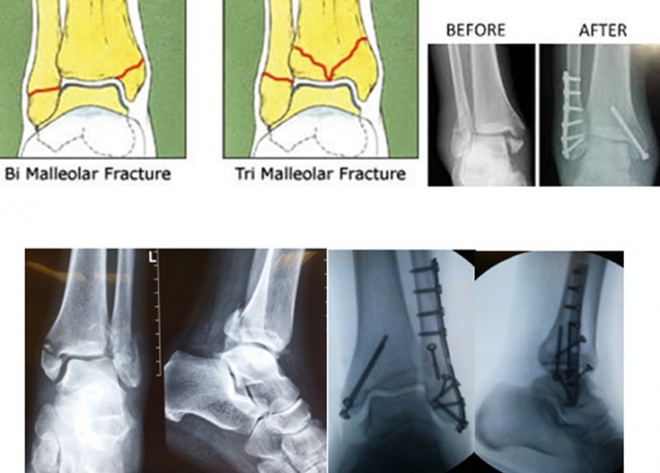

Από τα κατάγματα της ποδοκνημικής, το κάταγμα του έξω σφυρού συνήθως συνοδεύεται από κάταγμα και του έσω σφυρού (αμφισφύριο).

Το κάταγμα του έσω σφυρού συνοδεύεται από ρήξη του δελτοειδούς συνδέσμου.

Αυτό συμβαίνει γιατί τα δύο οστά συγκροτούν μία κολώνα με δύο στηρίγματα. Όταν σπάσει η μία κάπου, πρέπει να σπάσει και η άλλη (καμιά φορά αντί να σπάσει, κόβεται ο δελτοειδής σύνδεσμος ή υφίσταται κάταγμα η κεφαλή της περόνης στο γόνατο (κάταγμα Maisonneuve).

Η αντιμετώπιση ενός κατάγματος σφυρών, αμφισφυρίου ή τρισφυρίου (εάν έχει ξεκολλήσει κι ένα κομμάτι του πίσω τμήματος της κνήμης) είναι χειρουργική, ώστε να αναταχθεί το εξάρθρημα και να επανέλθει η ανατομική της άρθρωσης.